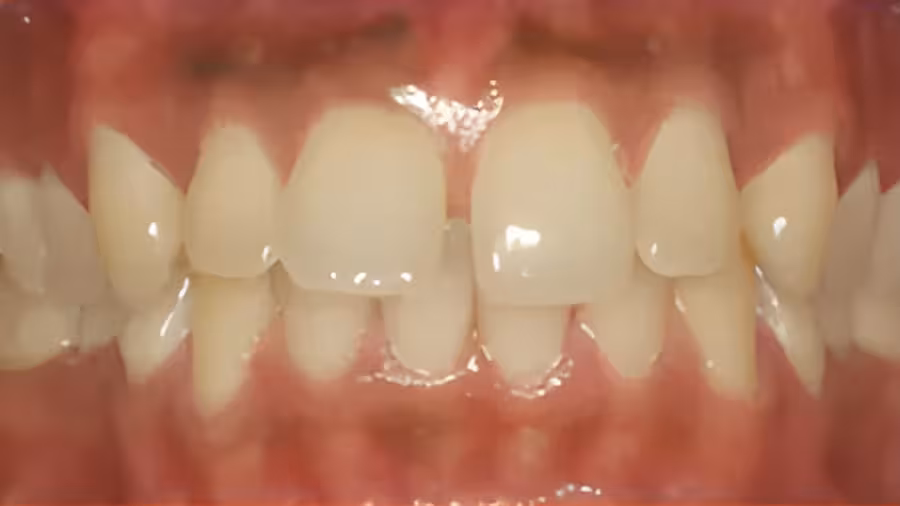

This patient had a deep overbite with upper and lower crowding corrected to proper alignment.